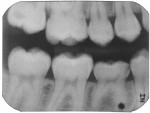

A 13-year-old girl had a retained ankylosed mandibular right primary second molar (Figure 1). The tooth had occlusal caries. In addition, a bitewing radiograph and lateral transillumination revealed a substantial caries lesion on the mesial surface (Figure 2). A panograph from a year prior (not pictured) showed congenital absence of the second premolar.